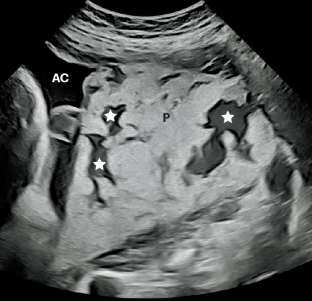

Jauniaux, E., Zosmer, N., D’Antonio, F. & Hussein, A. M. Placental lakes vs lacunae: spot the differences. Ultrasound Obstet. Gynecol. 63, 173–180 (2024).

Jauniaux, E., Collins, S. L. & Burton, G. J. Placenta accreta spectrum: pathophysiology and evidence-based anatomy for prenatal ultrasound imaging. Am. J. Obstet. Gynecol. 218, 75–87 (2019).

Jauniaux, E. et al. Delphi consensus expert panel. modified delphi study of the ultrasound signs associated with placenta accreta spectrum. Ultrasound Obstet. Gynecol. 61, 518–524 (2023).

Shainker, S. A. et al. Special report of the society for maternal–fetal medicine placenta accreta spectrum ultrasound marker task force: consensus on definition of markers and approach to the ultrasound examination in pregnancies at risk for placenta accreta spectrum. Am. J. Obstet. Gynecol. 224, B2–B14 (2021).